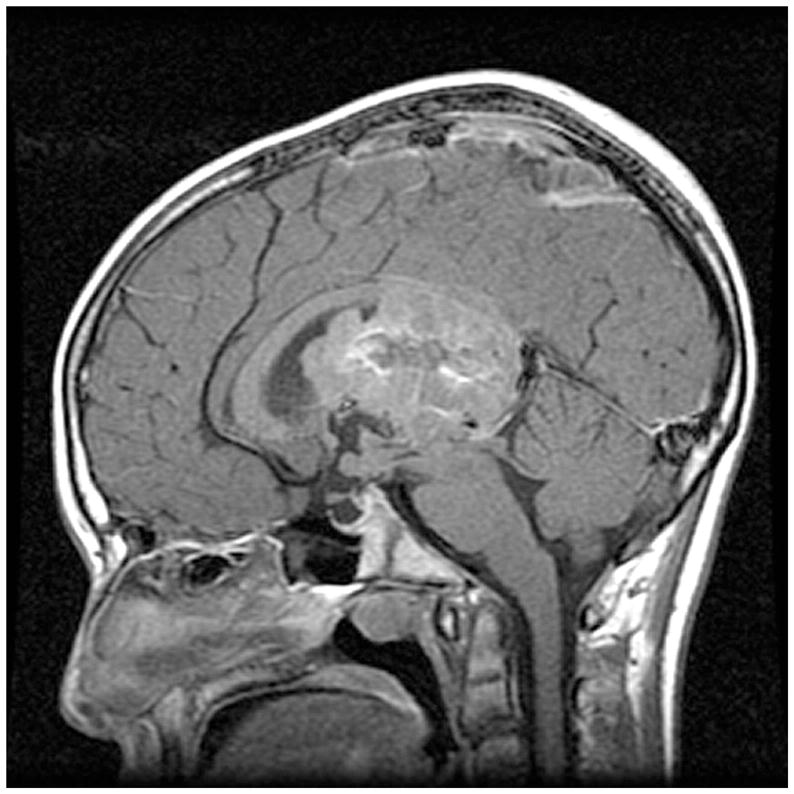

脑积水是神经外科常见的病症之一,是指颅内的脑脊液液体异常积聚,由于脑脊液的流动受阻或其产生与吸收不平衡引起,此外还有炎症反应、神经元损伤和室周轴突损害。 脑脊液生成...